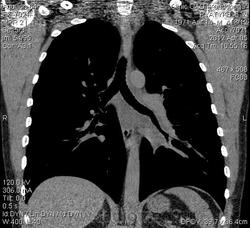

Мужчина, 41 год. Обследуется амбулаторно, вызван по результатам ФЛГ. На данный момент жалоб не предъявляет.

An.morbi: в 1990 году впервые на ФЛГ  выявлены изменения в нижней доле левого легкого, обследован в торак.отд. РБ, выполнялась бронхоскопия, диагносцирован постпневмонический пневмофиброз. В 1994 г перенес двустороннюю пневмонию.   В январе 2012 г перенес пневмонию слева в S4,5 с положительной динамикой (в том числе и рентгенологической) на фоне проводимой неспециф.  противовоспалительной терапии. На контрольной ФЛГ через 1,5 месяца были заподозрены "свежие очаги, усиление и сгущение легочного рисунка в н/отделах слева", в связи с чем и направлен на МСКТ грудной полости.   Клинич.и биохим. анализы крови в норме.

Слева легочный рисунок усилен за счет сосудистого компонента, равномерное утолщение стенок бронхов верхней и нижней долей с уменьшением их внутреннего диаметра, утолщение междольковых перегородок - интерстиц. отек? Увеличение объема клетчатки корня левого легкого и средостения - структура ее однородна, плотность от -5 до 5 HU. Жидкости в плевральной полости не выявлено. Имеется небольшой перикардиальный выпот.